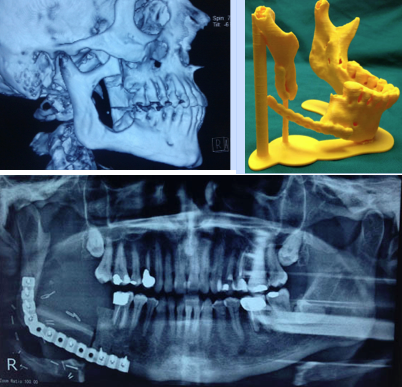

Οι τεχνικές αναδόμησης μπορεί να είναι ελάχιστα επεμβατικές με τοποθέτηση υλικών – μοσχευμάτων διαφόρων ειδών, LASER, ή χειρουργικές. Ο κύριος λόγος αναδόμησης του προσώπου αφορά αισθητικές απαιτήσεις όπου αποτελούν και τον μεγαλύτερο αριθμό. Δεν είναι όμως λίγες και οι παρεμβάσεις που αφορούν τους τραυματισμούς (πχ ατυχήματα τροχαία, εργατικά, αθλητικά, βιαιοπραγίες) και τα σύνδρομα.

Σε περιπτώσεις μορφωμάτων του προσώπου συχνά χρησιμοποιούνται υγιείς γειτονικοί ιστοί (κρημνοί) δέρματος ή μοσχεύματα δέρματος. Σε μεγάλα ελλείμματα όπως σε νεοπλάσματα, μπορεί να χρησιμοποιηθούν με ελεύθερη μεταφορά μεγαλύτερου μεγέθους ιστοί, (πχ δέρμα, μυς ή/και οστά), από ένα διαφορετικό μέρος του σώματος και ονομάζονται ελεύθεροι αγγειούμενοι κρημνοί.